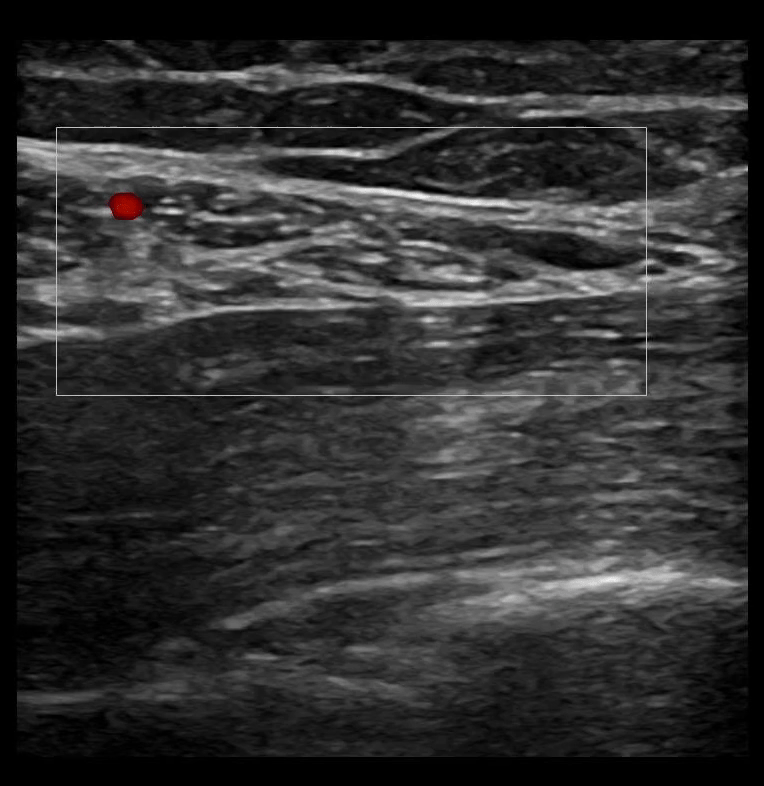

SAPB 2: The latissimus dorsi muscle sits superficial to the serratus anterior muscle. A color box on the latissimus dorsi muscle identifies vasculature.